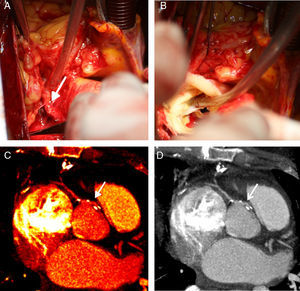

Angiografia coronária; painel A (incidência OAD30°; caud20.°) demonstrando a coronária esquerda sem lesões epicárdicas; painéis B (incidência OAE20°; cran20°) e C (OAD30°) demonstrando a coronária direita sem lesões epicárdicas e com origem na parede ântero-lateral esquerda da aorta, acima dos seios coronários.